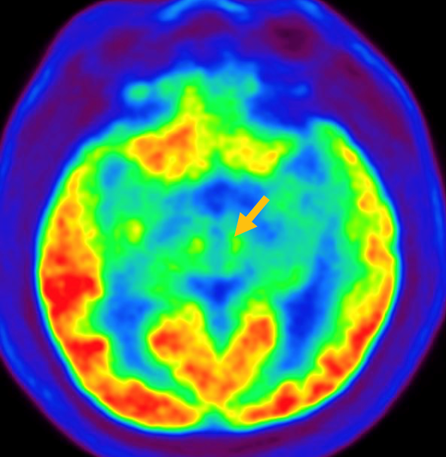

피질 기저핵 변성은 비대칭 증상을 두드러지게 보인다는 점에서 파킨슨병과 비슷합니다. 그러나 파킨슨병과 비교해 보았을 때 양측의 차이가 아주 심하게 나타난다는 특징이 있습니다. 질병 초기에 한쪽 손으로 동작을 하거나 계획된 행동을 하는 기능이 현저하게 떨어집니다. 간단한 손가락 모양도 따라 하지 못하는 현상을 보입니다. 또한 의지와 상관없이 제멋대로 움직이는 통제불능 손이 나타날 수 있습니다. 체위 떨림, 경축, 운동 완만과 같은 파킨슨병에서 볼 수 있는 증상들은 피질 기저핵 변성에서도 관찰될 수 있습니다. 또한 집중력 장애, 수행 장애, 이름 대기나 언어의 유창성이 떨어지는 등 전두엽 및 두정엽과 관련된 인지 장애가 나타납니다. 피질 기저핵 변성은 뇌 자기공명영상(MRI)에서 증상의 반대쪽 전두두정엽의 위축 소견이 특징적으로 나타납니다. 뇌포도당 양전자 단층촬영(PET)에서도 전두엽, 뇌기저핵에 비대칭적인 대사 저하의 소견이 보입니다.

[피질기저핵 변성 환자의 뇌포도당 양전자 단층촬영에서 확인되는 비대칭적인 대사 기능 저하]